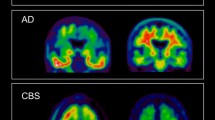

Molecular imaging can also facilitate the differential diagnosis among PD, atypical parkinsonian syndromes (APS), essential tremors, and other degenerative conditions that represent a group of complex and heterogeneous diseases with overlapping symptomatology and variable response to dopaminergic medications. 123I-FP-CIT SPECT can distinguish degenerative forms of parkinsonism from essential tremor [44], drug-induced parkinsonism [45] and could also differentiate DLB from AD. Subjects with PD and APS show indeed an early reduction of striatal dopaminergic binding [46] usually before the appearance of motor symptoms. On the contrary, patients with essential tremor, drug-induced parkinsonism, and AD are characterized by normal dopamine transporter uptake [47]. Although a differential pattern has been described at the group level, a real distinction between the various degenerative forms of parkinsonism is not possible by means of SPECT assessment only. To this purpose, 18F-FDG PET has demonstrated to be more promising. As suggested by Albrecht et al. [48], glucose hypometabolism at 18F-FDG PET can identify consistent functional brain abnormalities in PD, outperforming structural MRI. In particular, while MRI showed only focal and inconsistent alterations, in PD patients the authors found an extensive glucose hypometabolism in bilateral inferior parietal cortex and left caudate nucleus that is related to cognitive deficits (inferior parietal cortex) and motor symptoms (caudate nucleus). Disease-specific patterns of regional glucose metabolism in patients with parkinsonism are well documented [49, 50]. However, the valuable capability of 18F-FDG PET for accurate differentiation between PD and APS has been unanimously accepted only in recent years. In a preliminary meta-analysis, Meyer et al. well described the different 18F-FDG uptake pattern in PD and APS [51]. PD is characterized by a posterior temporoparietal, occipital, and sometimes frontal hypometabolism with a relative hypermetabolism of the putamen, pallidum, thalamus sensorimotor cortex, pons, and cerebellum.

MSA patients show instead a marked hypometabolism of the putamen (mainly in its posterior portion), pons, and cerebellum, which may be more pronounced in the striatum or in the pons and cerebellum, on the basis of the clinical presentation. Conversely, PSP is characterized by a regional hypometabolism preferentially involving the medial, dorsal, and ventrolateral frontal areas (i.e., the anterior cingulate gyrus, supplementary motor area, precentral gyrus, and premotor-to-posterior prefrontal areas); caudate, thalamus, and upper brain stem. Finally, CBD patients have a typically highly asymmetric hypometabolism of the frontoparietal areas, striatum, and thalamus contralateral to the most affected body side. A concomitant cortical hypometabolism may be mainly found in the parietal cortex and usually extends across the sensorimotor cortex into the cingulate gyrus and premotor-to-posterior prefrontal areas.